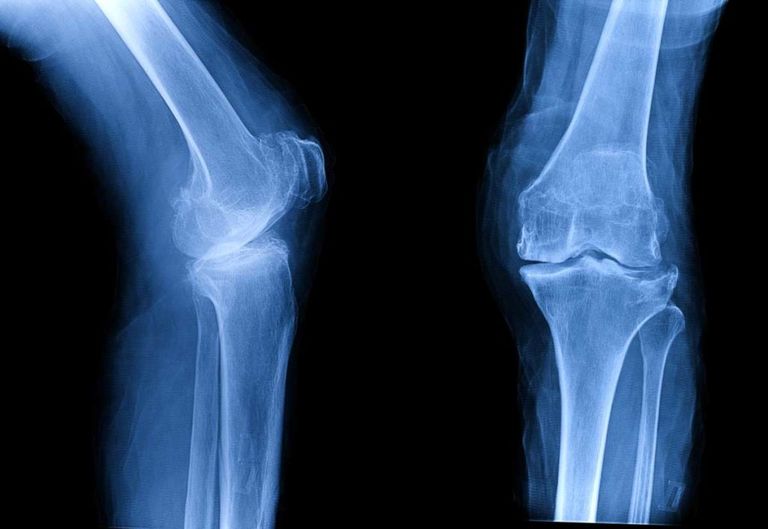

وبقيادة البروفيسور تو ييهينج من معهد علم النفس التابع للأكاديمية الصينية للعلوم، سلطت النتائج التي توصل إليها الفريق الدولي الضوء على التأثيرات المعرفية العصبية العميقة للألم العضلي الهيكلي المزمن، وخاصة آلام الركبة المزمنة، مثل التهاب مفاصل الركبة.

وكشف تحليلهم أن الأفراد الذين يعانون من التهاب مفاصل الركبة، يعانون من تسارع شيخوخة الدماغ مقارنة بنظرائهم الأصحاء.